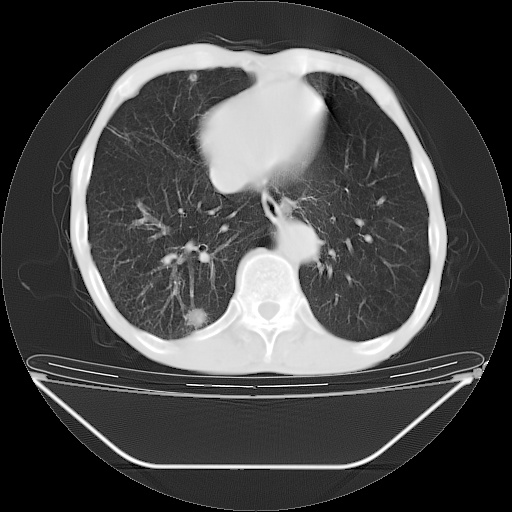

以下是引用zsl6918在2008-8-25 21:55:00的发言:[br]符合右肺周围性肺癌并肺内转移,左肺结核球。双肺肺气肿。腰椎附件转移。

以下是引用随光逐影在2008-8-25 22:03:00的发言:[br]1)考虑右肺下叶周围性肺癌并肺内转移,腰椎附件转移。2)左上肺结核(结核球形成)。3)双肺肺气肿(多发肺大泡形成)。4)双肺门区及纵隔内多发淋巴结钙化。